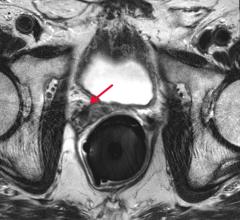

As radiologists, most of us have seen firsthand how dense breast tissue can mask cancer in mammography. As breast density increases, mammography sensitivity decreases and breast cancer risk elevates, highlighting the need for optimal approaches to individualized breast cancer screening.

Despite decades of progress in breast imaging, one challenge continues to test even the most skilled radiologists ...